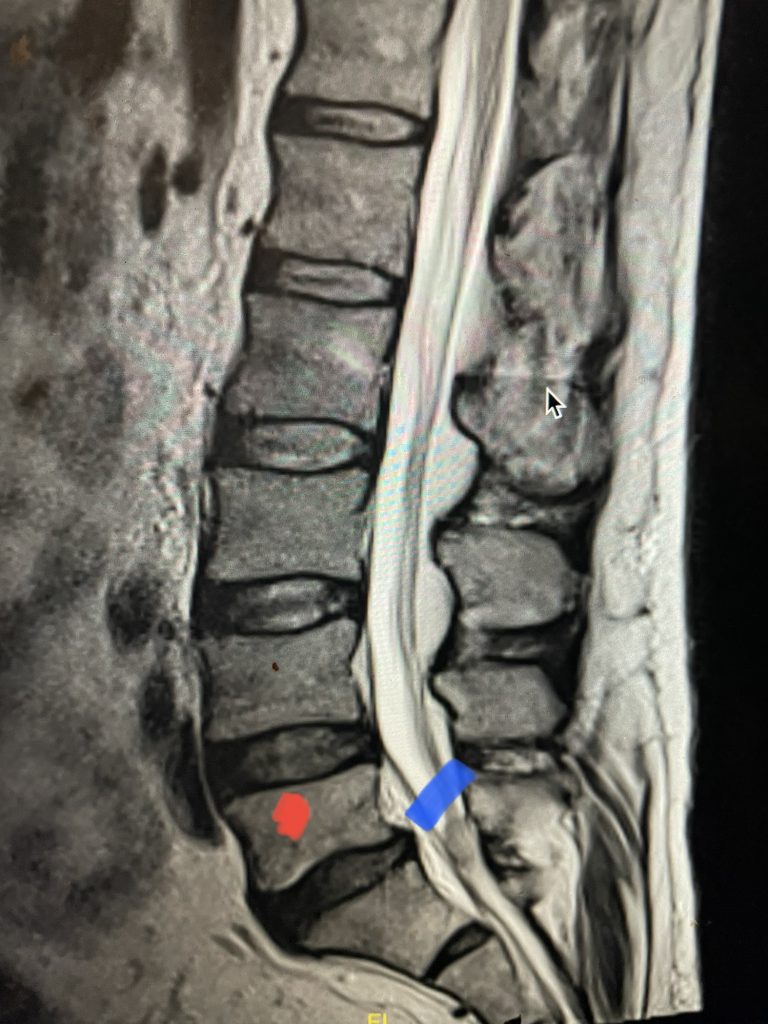

Here is a dramatic example of a patient who had prior laminectomy and fusion surgery four years earlier, and now presents with low back pain with severe burning pain in her right lower extremity pain. She did not respond to epidural steroids. She had a prior L3-S1 laminectomy, and an L3-5 instrumented fusion. A current MRI (Fig 4) demonstrated severe L2-3 next segment stenosis due the development of massively hypertrophied or enlarged L2-3 joint complexes. There was also a grade 1 retrolisthesis of L2 on L3 with a large anterior disc osteophyte complex. The configuration of the stenosis was worse in the right lateral recess secondary to the anterior osteophyte and more right-sided facet compression of the thecal sac, correlating with the patient’s right-sided symptoms. When the anatomy correlates with the patient’s symptoms that is the best set up for success. It was decided to offer a revision surgery to the patient, who agreed.

Fig 4: Sagittal and axial T2-weighted lumbar MRI images demonstrating severe next segment degeneration and stenosis at L2-3 above prior L3-5 fusion. Note retrolisthesis and significant facet arthropathy at L2-3 (red arrow).